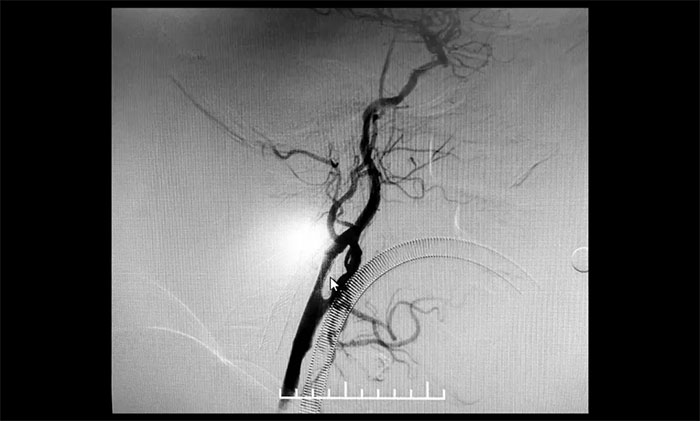

術(shù)后康復(fù)觀察一月余,于耀宇主任團(tuán)隊(duì)再次為曹老伯行右側(cè)頸動(dòng)脈支架置入及左側(cè)椎動(dòng)脈支架置入手術(shù)。術(shù)中造影顯示,右側(cè)頸內(nèi)動(dòng)脈起始段重度狹窄,狹窄長(zhǎng)度8mm左右。左側(cè)椎動(dòng)脈 V4 段重度狹窄,長(zhǎng)度6mm左右。運(yùn)用嫻熟扎實(shí)的技術(shù),在充分做好腦保護(hù)的前提下經(jīng)過(guò)多次球囊擴(kuò)張后,順利釋放支架于狹窄處。造影提示支架打開(kāi)良好,血管狹窄基本恢復(fù)正常,支架貼壁佳,支架內(nèi)血流通暢,遠(yuǎn)端血流良好。

▲ 術(shù)后,右側(cè)頸內(nèi)動(dòng)脈及左側(cè)椎動(dòng)脈狹窄明顯改善